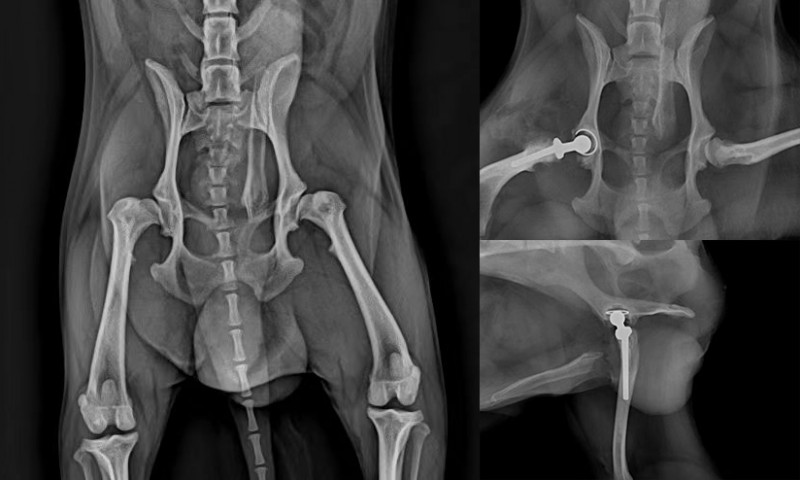

杜浪院长曾接诊一例3岁博美公犬,就诊前表现出双后肢无力、行动受限等症状。经系统体格检查与影像学评估,杜院长发现其双侧髋关节形态异常,活动度显著受限,最终确诊为“犬双侧髋关节发育不良”。

考虑到患犬比较年轻且生活质量受到严重影响,在与主人充分沟通后,杜院长决定实施全髋关节置换术,以重建关节功能、缓解疼痛并恢复肢体支撑力。

该病例的手术难度集中体现在两方面:其一,患犬髋臼增生磨损,呈典型“扁平髋”形态,对术中髋臼杯的定位与打磨精度提出极高要求;其二,股骨侧存在畸形的大转子结构,严重影响股骨柄植入的中心化与稳定性。面对这一复杂的关节重建挑战,杜浪院长凭借丰富的骨科经验与精准的术前规划,在术中成功完成髋臼修整等一些列操作,实现了生物学固定与力学对线。

手术顺利完成,患犬在术后恢复良好,肢体功能逐步改善,为后续对侧手术奠定了良好基础。

本例手术的难点不仅在于关节严重变形背景下的精准重建,更在于如何在有限的操作空间中兼顾力学稳定与长期愈合潜力。杜浪院长在此过程中展现出深厚的关节外科功底、对复杂骨结构的处理能力,以及在高难度择期手术中把握细节、控制风险的专家风范。

该病例也表明,对于严重的髋关节发育不良,全髋置换术是一项从根本上改善生活质量的有效治疗方式,而成功的关键在于精准的术前评估、熟练的手术技术以及系统的术后康复管理。